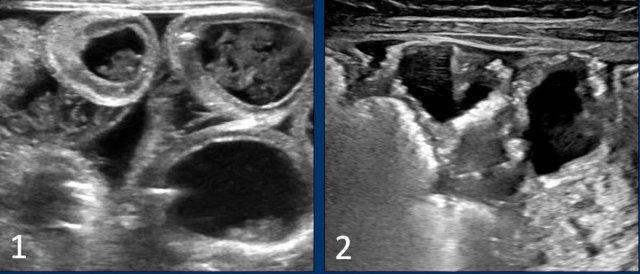

Doppler màu

Đánh giá thành ruột đòi hỏi một số kinh nghiệm.

Thành ruột bình thường có độ dày dưới 2,5 mm và có tín hiệu dòng chảy Doppler.

Thành ruột bệnh lý có biểu hiện dày lên (độ dày thành > 2,5 mm) và thành phù nề có tăng âm.

Có thể có tăng tín hiệu dòng chảy Doppler.

Điều này có thể khó đánh giá vì hầu hết trẻ sinh non bệnh nặng sẽ đang được hỗ trợ hô hấp và tín hiệu Doppler sẽ bị nhiễu bởi các xảo ảnh.

Trong bệnh tiến triển, khi ruột hoại tử hoàn toàn, thành ruột trở nên mỏng (độ dày thành < 1 mm) và không đều.

Tín hiệu dòng chảy Doppler sẽ giảm dần và cuối cùng mất hoàn toàn.

Hình ảnh

- Thành ruột bệnh lý: ruột dày và tăng âm, xen kẽ dịch cổ trướng.

- Thành ruột mỏng và không đều trong NEC tiến triển.

Hình ảnh Doppler cho thấy vắng mặt dòng chảy và sự hiện diện của khí trong thành ruột (pneumatosis intestinalis).

Hình ảnh được cung cấp bởi GS.TS. M Epelman, RadioGraphics 2007